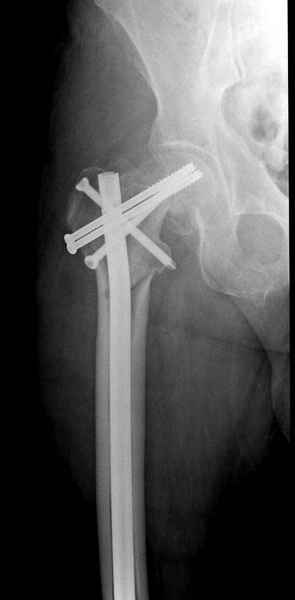

Правильно, ситуация изменилась, как говорят у нас теперь "different animal", надо решать проблему подвертельного перелома. При наличии различных вариантов фиксаторов, включая Страйкер Гамма 3, мы выбрали DePuy Antegrade Trachanteric Nail из-за многовариантности проксимальной фиксации и двойного изгиба. Вводится через вертел под 8 градусным углом, и есть достаточный передний диафизарный изгиб, предупреждающий пенетрацию дистального переднего кортекса.

Кто знает что дальше, мысленно готовы к проксимальной артропластике.

Но ведь и головка бедра сползла в варус - отчего ограничились только фиксацией подвертельного перелома, а не убрали винты и не сделали репозицию шейки?